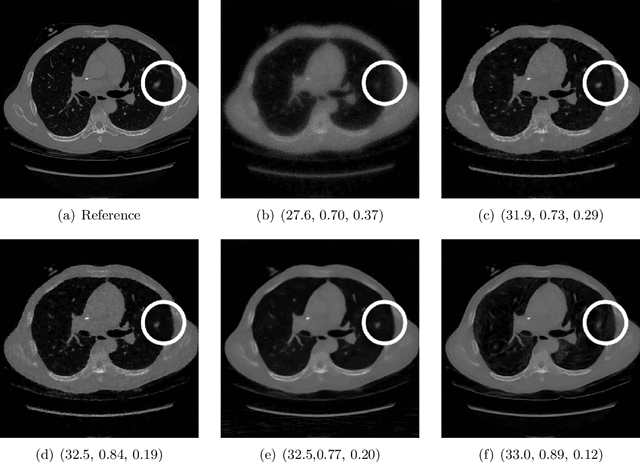

Abstract:Image quality assessment (IQA) is standard practice in the development stage of novel machine learning algorithms that operate on images. The most commonly used IQA measures have been developed and tested for natural images, but not in the medical setting. Reported inconsistencies arising in medical images are not surprising, as they have different properties than natural images. In this study, we test the applicability of common IQA measures for medical image data by comparing their assessment to manually rated chest X-ray (5 experts) and photoacoustic image data (1 expert). Moreover, we include supplementary studies on grayscale natural images and accelerated brain MRI data. The results of all experiments show a similar outcome in line with previous findings for medical imaging: PSNR and SSIM in the default setting are in the lower range of the result list and HaarPSI outperforms the other tested measures in the overall performance. Also among the top performers in our medical experiments are the full reference measures DISTS, FSIM, LPIPS and MS-SSIM. Generally, the results on natural images yield considerably higher correlations, suggesting that the additional employment of tailored IQA measures for medical imaging algorithms is needed.

Abstract:Image quality assessment (IQA) is not just indispensable in clinical practice to ensure high standards, but also in the development stage of novel algorithms that operate on medical images with reference data. This paper provides a structured and comprehensive collection of examples where the two most common full reference (FR) image quality measures prove to be unsuitable for the assessment of novel algorithms using different kinds of medical images, including real-world MRI, CT, OCT, X-Ray, digital pathology and photoacoustic imaging data. In particular, the FR-IQA measures PSNR and SSIM are known and tested for working successfully in many natural imaging tasks, but discrepancies in medical scenarios have been noted in the literature. Inconsistencies arising in medical images are not surprising, as they have very different properties than natural images which have not been targeted nor tested in the development of the mentioned measures, and therefore might imply wrong judgement of novel methods for medical images. Therefore, improvement is urgently needed in particular in this era of AI to increase explainability, reproducibility and generalizability in machine learning for medical imaging and beyond. On top of the pitfalls we will provide ideas for future research as well as suggesting guidelines for the usage of FR-IQA measures applied to medical images.